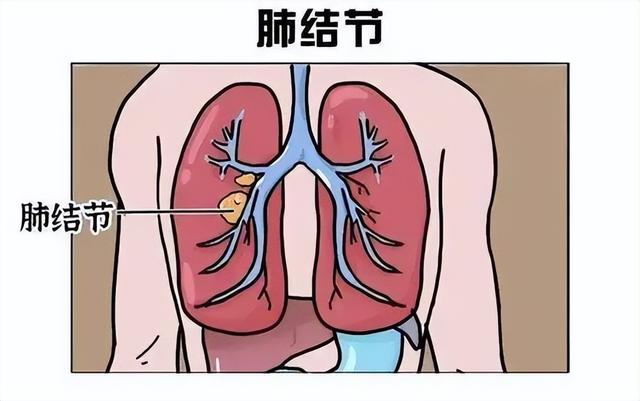

首先我们要了解什么是肺结节?肺结节并不特指某种疾病,为疾病在胸部影像学中表现,病变通常表现为直径≤3cm、周围被含气肺组织包绕、边界清晰的实性或亚实性病变,肺结节不伴肺门肿大与胸腔积液。肺结节既有可能是良性结节,也有可能是恶性结节,也就是癌性结节。良性结节具有良性病灶的特征,为肺部陈旧性病变或者炎性增殖性病变,也就是不会发生癌变,不会转变为癌。恶性结节本身是癌性病变,不存在癌不癌变的问题。恶性结节大多是早期肺腺癌,绝大部分没有出现转移,及早治疗可以达到很高的治愈率。

肺结节分为磨玻璃结节、部分实性结节和实性结节三种情况,其中部分实性结节恶性程度最高最容易发展为肺癌,而磨玻璃结节和实性结节如果大于8mm,也要警惕是否发生肺癌,所以肺部恶性结节的发生主要与部分实性结节有关。